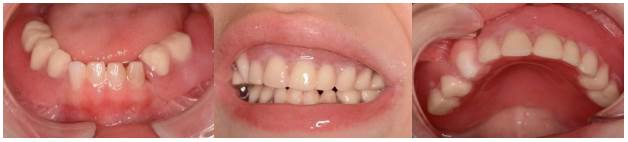

Al examen clínico de la cavidad bucal (Figuras 2, 3 y 4) no se observaron lesiones en las mucosas, se certificaron quince dientes temporarios ausentes (55-54-52-51-61-62-63-64-65-73-74-75-83-84-85) y cinco dientes temporarios con lesiones de caries (53-71-72-81-82); presencia generalizada de biopelícula sobre las superfícies dentarias, sangrado gingival provocado al sondaje, saliva abundante, lengua voluminosa, desbordante e hipotónica y bridas y frenillos sin particularidades.

En relación al examen radiográfico, la radiografía panóramica inicial (Figura 5) mostró ausencia de muchos dientes temporarios, y también se observó presencia de gérmenes de dientes permanentes y retraso en la erupción dentaria de algunos dientes, lo que requería un acompañamiento.